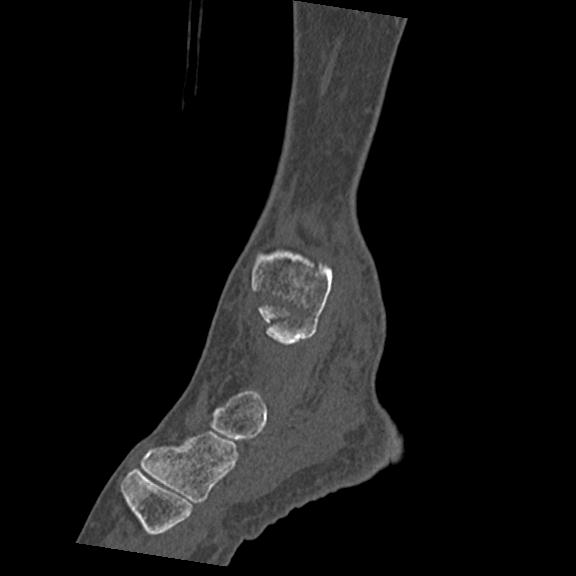

102755 1/4 2R 1/15 2R 右足関節 68歳女性 右三果脱臼骨折

56476 8/28 4R 1/21 2R 左足関節 デジカメ写真 72歳女性 右足関節AS